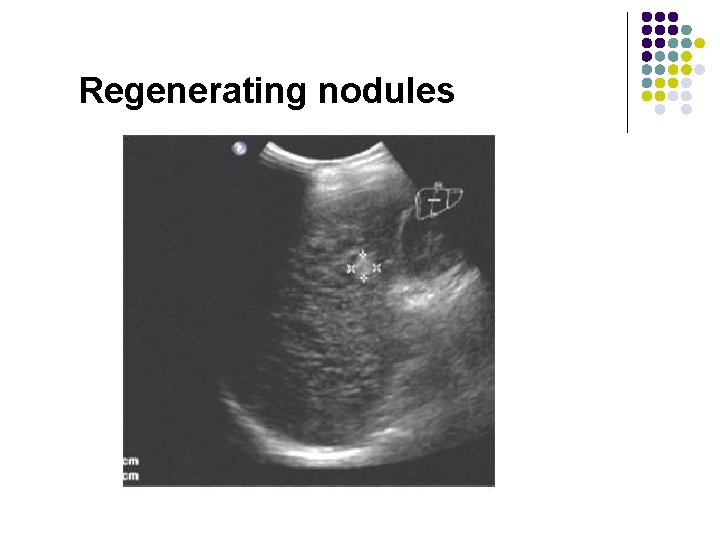

Regenerating nodules

Regenerating nodules